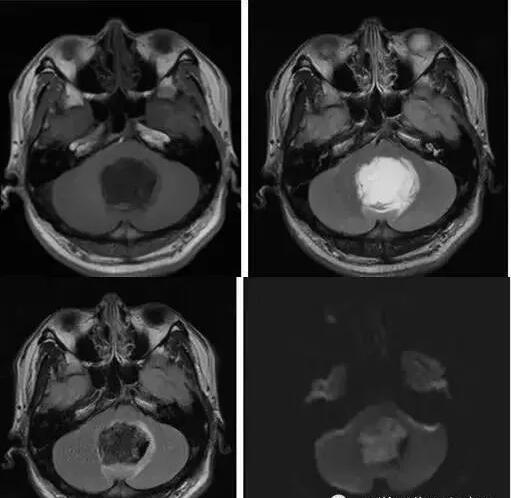

MR表現(xiàn):

①鞍上池或橋小腦角池類圓形或不規(guī)則病變,邊緣銳利。

②T1加權(quán)絕大部分為均勻的低信號,少數(shù)由于瘤體內(nèi)含液態(tài)膽固醇或出血而呈高信號影。T2加權(quán)呈明顯的、均勻一致的高信號影,高于腦脊液信號;DWI可見高信號。

③腫瘤包膜于T1加權(quán)呈中等信號,T2加權(quán)呈高信號影。

④增強(qiáng)檢查無強(qiáng)化效應(yīng)。